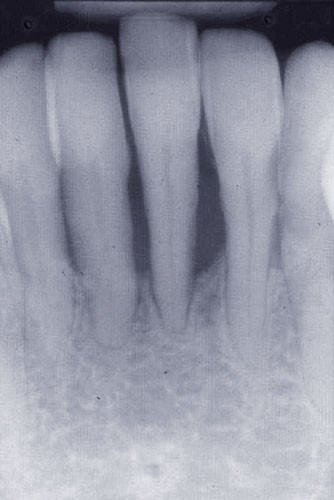

Une patiente âgée de 45 ans consulte à la fin des années 1990 avec une contention en échelle au maxillaire afin de soulager les mobilités des dents antérieures.

Les examens cliniques et radiographiques montrent une parodontite chronique généralisée (fig. 1a à m).